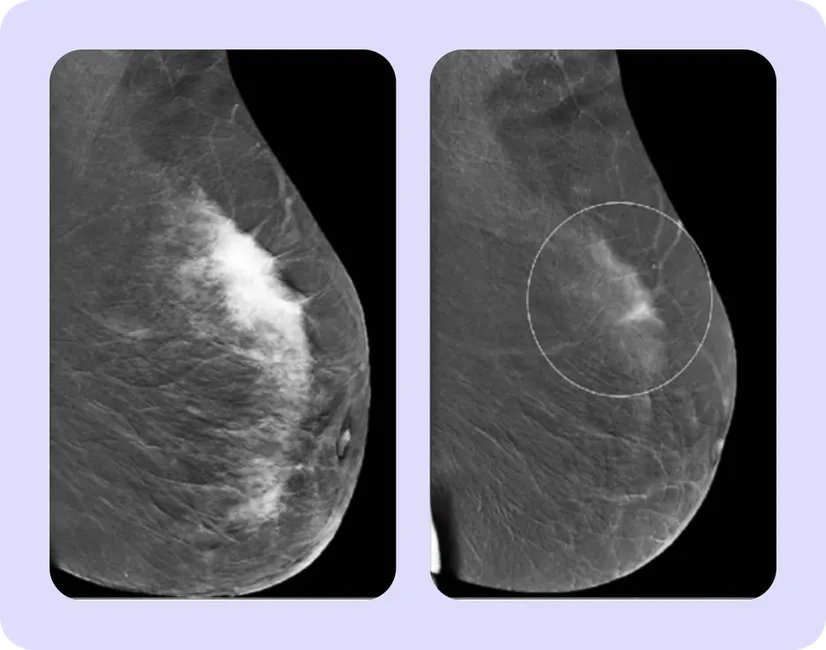

Об эффективности терапии говорит уменьшение размера опухоли. Для этого перед началом лечения врачи измеряют размеры новообразования, метастазов в лимфатических узлах с помощью маммографии или ультразвукового исследования (УЗИ). В некоторых случаях может использоваться магнитно-резонансная томография (МРТ). После завершения предоперационной терапии, исследования проводятся повторно, чтобы понять, как изменились размеры и распространенность опухоли9.

На первом изображении представлен пример полного ответа. Очаг уменьшился настолько, что перестал быть заметен на МРТ. Во втором случае наблюдается частичный ответ: очаг значительно уменьшился, но не исчез совсем10,11. МРТ лишь дополнительный метод исследования, ее проводят далеко не всем пациентам на неоадьювантной терапии, но в целях демонстрации эффекта мы выбрали именно этот метод.